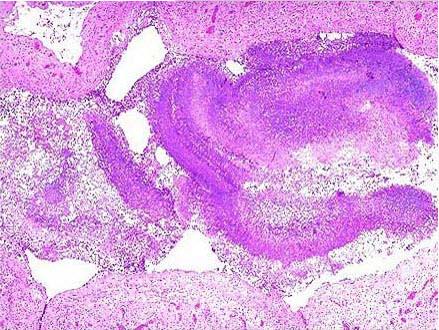

这篇文章的“新”并不在于“发现新器官”,而是首次采用了一种新的技术方法——激光共聚焦显微内窥镜检测法,观察了一些已存在的组织结构。以往人们观察这些组织时需要先采样,再经过一系列处理和染色,制作成组织切片放到显微镜下观察,这些处理过程破坏了间质的原有结构,导致间质由于失水而变得“干瘪皱缩”。而激光共聚焦显微内窥镜可以直接对人体组织进行实时观测,不会破坏组织形态,由此间质原本充满流动液体的结构终于被完整地呈现在屏幕上。与其说“发现了间质”,不如说“看清了间质”更恰当。